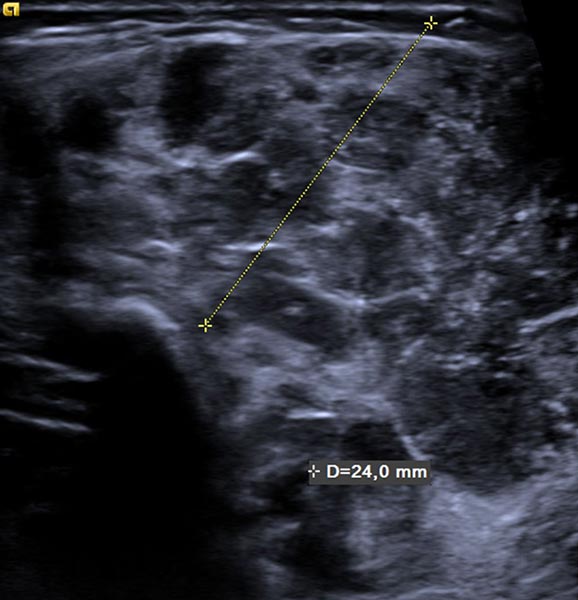

Ab der 2. Lebenswoche waren bei dem Säugling insgesamt 8 kleine kutane infantile Hämangiome typischer Art langsam wachsend an der Haut sichtbar. Zusätzlich eine umschriebene, langsam größer werdende Schwellung ventral in der Mitte des linken Oberarmes. Die darüber liegende Haut war nicht verfärbt. In der hier abgebildeten B-Bild-Sonographie dieser Stelle, im Verlauf Ende des 4. Lebensmonats, zeigt sich ein relativ echoarmer Tumor im Subkutangewebe.

Die entsprechende B-Bildsonographie Ende des 8. Lebensmonats zeigt neben der Volumenzunahme auch deutlich vermehrte echoarme Anteile in dem Tumor. Dies entspricht Zellproliferaten und ist ein Merkmal eines in Proliferation befindlichen infantilen Hämangioms, kann aber auch bei anderen vaskulären Tumoren vorkommen.